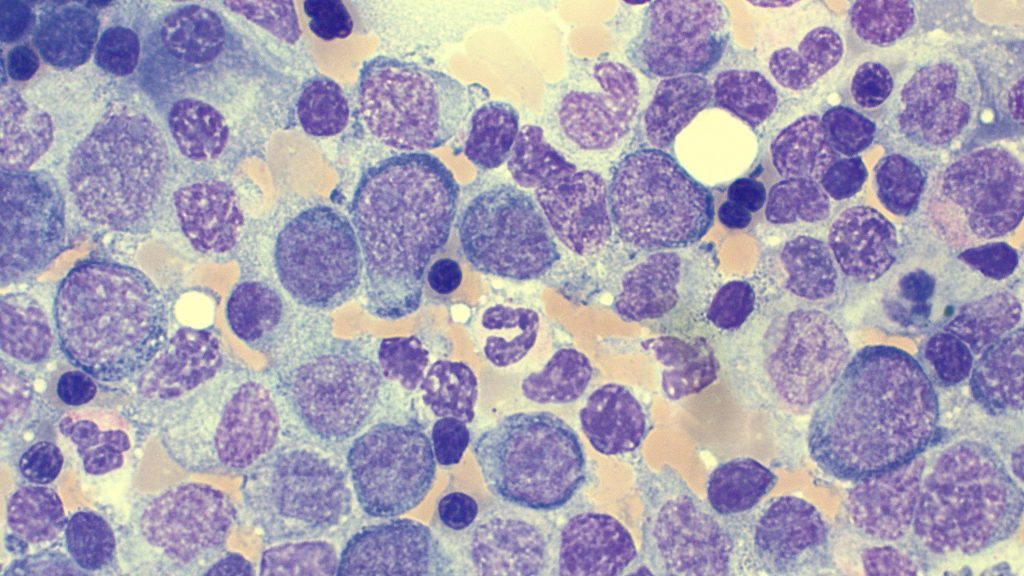

Multiple Myeloma

Myeloma Cells

More…